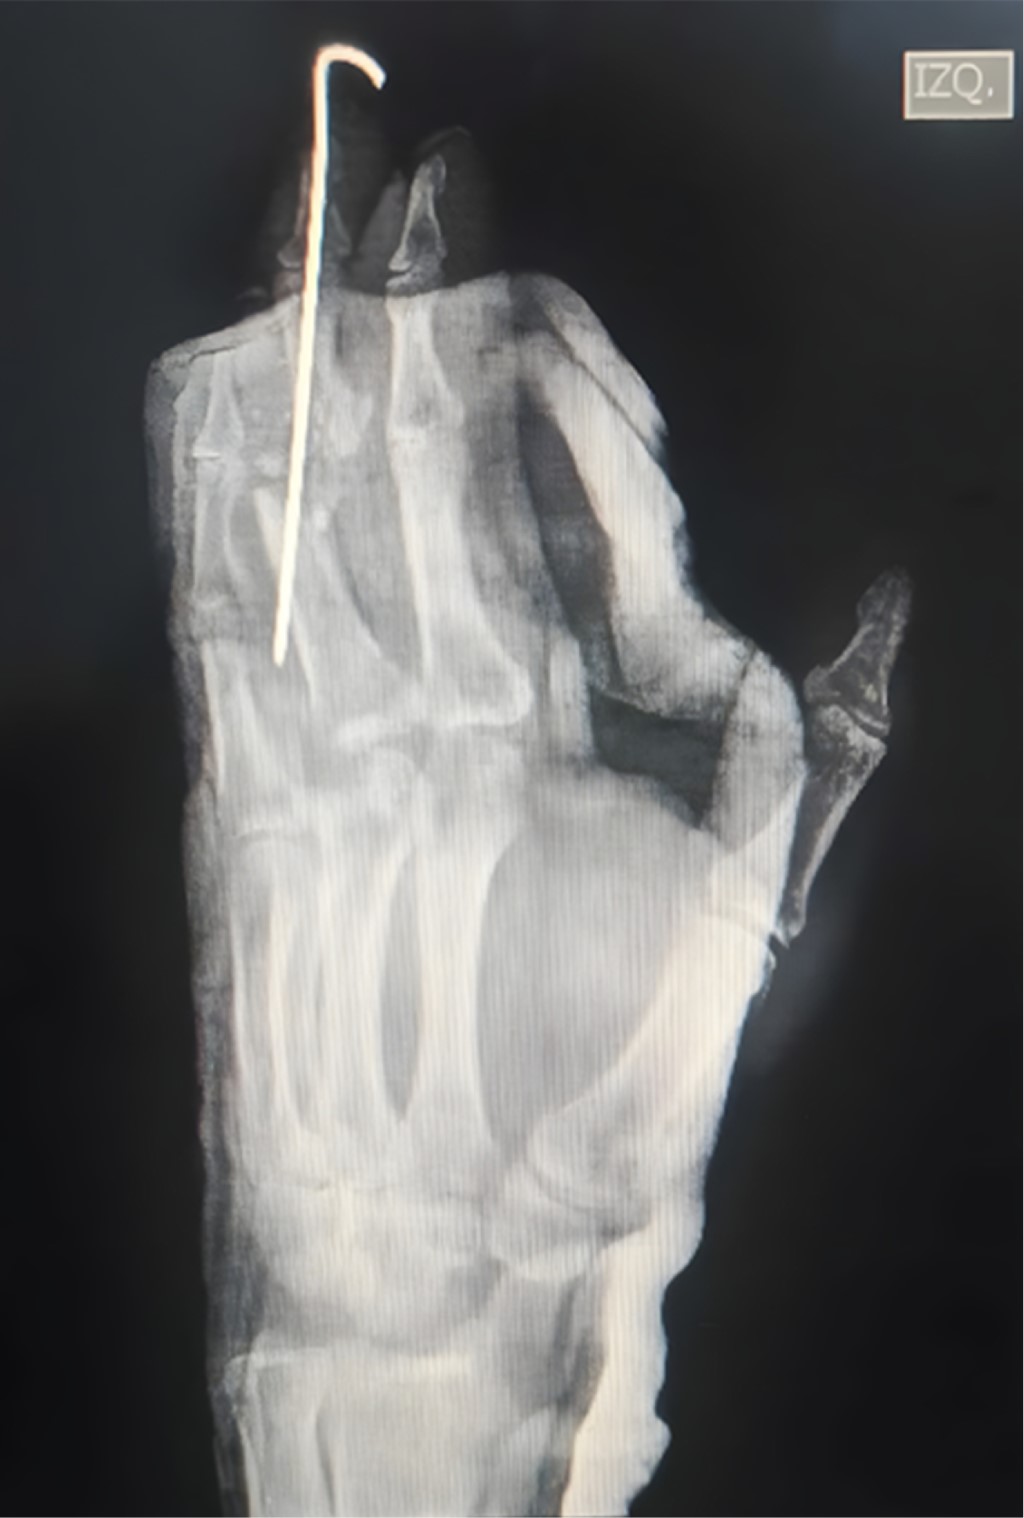

Paciente masculino de 48 años de edad, quien ingresa a nuestra unidad hospitalaria tras presentar lesión en mano izquierda posterior a carga axial, así como compresión al ser arrollado por vehículo automotor; a su ingreso, se identifica incongruencia articular en las líneas de Gilula (Figuras 1 y 2).

Además de presentar fractura en metáfisis proximal con extensión a metáfisis distal de F2 de tercer dedo, amputación traumática con desarticulación de F1-F2 más denudamiento de cuarto dedo, herida cruenta de quinto dedo más lesión del extensor propio del quinto dedo en zona V. A su ingreso pasa a cirugía de control de daños más reducción cerrada de luxación peri-escafo-transtrapecio-transtrapezoidea (Figura 3).

Durante su estancia se manejó con impregnación antibiótica más analgesia; posterior a la impregnación antibiótica, pasa a procedimiento definitivo donde se realizó carpectomía de muñeca izquierda (Figuras 4 y 5) con artrodesis de articulación interfalángica de F2-F3 tercer dedo (Figura 6) más tenorrafia de extensor propio de quinto dedo (Figura 7) y colgajo de herida cruenta en quinto dedo (Figura 8).